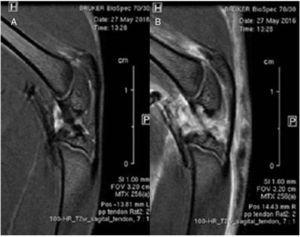

In vivo 1H-magnetic resonance imaging (MRI) studies were performed at the Autonomous University of Barcelona (UAB, Barcelona, Spain) using a 7T Bruker BioSpec 70/30 USR (Bruker BioSpin GmbH, Ettlingen, Germany) system equipped with a mini-imaging gradient set (400mT/m) and using a quadrature transceiver volume coil with 72 mm inner diameter.

Rats were positioned in a bed, which allowed delivery of anesthesia (isoflurane, 1.5-2.0% in O2 at 1 L/min), with an integrated heat water circuit for body temperature regulation (Fig. 2). Body temperature was measured with a rectal probe and maintained at 37 ± 1 ¿C. Respiratory frequency was monitored with a pressure probe and kept between 60 and 80 breaths/min. Low resolution T2-weighted fast spin-echo images were initially obtained in axial, sagittal and coronal planes to be used as reference scout images. Imaging parameters for these images were: effective echo time (TEeff) = 36 ms; repetition time (TR) = 3 s; echo train length (ETL) = 8; field of view (FOV) = 6 × 6 cm2; matrix size (MTX) = 128 × 128; slice thickness (ST) = 2 mm; gap between slices (gap) = 0.5 mm; number of slices (NS) = 25 — axial, 10 — sagittal, 11 — coronal; number of averages (NA) = 1. High resolution T2-weighted fast spin-echo images were acquired afterwards in sagittal planes containing the lesion and the contralateral side. Experimental parameters for these images were: TEeff = 30 ms; TR = 4 s; ETL = 8; FOV = 3.2 × 3.2 cm2; MTX = 256 × 256; ST = 1 mm; gap = 0.1 mm; NS = 18; NA = 12; experimental time = 25 min 36 s. MRI data were acquired and processed on a Linux computer using Paravision 5.1 software (Bruker BioSpin GmbH, Ettlingen, Germany).

Figure 2 Anestesized animals were monitored for temperature and respiratory frequency during MRI analysis. High resolution T2-weighted fast spin-echo sagittal images were acquired of the injured and contralateral patellar tendons.

MRI sagittal images of healthy and injured patellar tendons were compared. No differences were detected in the alignment or thickness of tendon fibers along the tendon tissue. Diffuse edema affecting mainly the articular and muscular structures was observed (Fig. 3).

Figure 3 Comparative study using magnetic resonance imaging. No differences were found in the structure of the healthy patellar tendon (A) and in the injured tendon (B).

There are some limitations in our study. The first one is the small amount of animals (N = 4) used for the study. Second, the dose of collagenase should be optimized in order to exactly reproduce the characteristic changes in human patellar tendinopathy and prevent the collateral damage of adjacent structures to the tendon. Perucca Orfei et al.45 generated a model in rat Achilles tendon which closely reproduced the histological changes observed in human Achilles tendinopathy. They evaluated the effect of two doses of intra-tendinous delivered collagenase (1 and 3 mg/ml). Although both doses induced disorganization of collagen fibers and increased cellularity, the higher collagenase dose treatment was able to induce a greater neovascularization and fat degeneration, being also time-dependent changes. In our study, these changes were not observed since the time elapsed from collagenase administration to tendon analysis was shorter. In addition, Perucca Orfei et al. exposed the tendon by a longitudinal incision of the skin, whereas we used a minimally invasive technique based on ultrasound-guided collagenase administration in order to induce tendinopathy in the specific proximal deep fibers region of the patellar tendon with the minimal disturbance of the structures and tissues of the knee joint. Moreover, our analysis performed by magnetic resonance demonstrates that the effect of collagenase is not localized exclusively at the tendon level but could also affect periarticular structures, a situation which has not been discussed in previous studies.